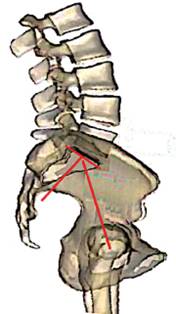

Incidencia pélvica. Legaye36 introdujo el concepto de «incidencia pélvica» definiéndola como el ángulo formado entre la línea perpendicular al platillo sacro en su punto medio y la línea que conecta este punto con el eje de las cabezas femorales (Figuras 13 y 15). Es una herramienta radiológica que sirve para evaluar el balance sagital espino-pélvico interrelacionado principalmente dos factores: a) la pendiente sacra y b) la posición de las cabezas femorales.

La importancia de esta medición en cirugía de cadera radica en el hecho de que el fulcro de la rotación (inclinación) pélvica son las cabezas femorales. Y cuando éstas se alejan o acercan a la línea de gravedad sagital, no sólo se puede alterar el equilibrio sagital global, por añadidura también la orientación del acetábulo. Para alcanzar un equilibrio sagital óptimo, debe alinearse el centro de las cabezas femorales con la línea de gravedad sagital. Entre más se acerquen mejor equilibrio sagital se logra. Observe en la Figura 16 que hay francas alteraciones estructuradas de la columna vertebral y que hay una amplia incidencia pélvica por lo que la pelvis rota hacia adelante, alejando el eje bicoxofemoral del centro de gravedad.

En población normal, la incidencia pélvica puede variar de 33o a 85o y se incrementa en promedio 22o al pasar de la posición sentado a la posición supina o de pie.35 Una incidencia baja (< 44o) disminuye la pendiente sacra y la lordosis se aplana. Una alta incidencia (> 62o) aumenta la pendiente sacra y la lordosis es más pronunciada.37

Es oportuno abrir aquí un paréntesis para definir qué es el «eje bicoxofemoral». Debido a que en una radiografía lateral es muy difícil hacer coincidir los centros de rotación de ambas cabezas femorales, se utiliza el concepto de «eje bicoxofemoral». Este eje se localiza en la parte media de una línea trazada entre los centros de rotación de ambas cabezas femorales en una radiografía lateral espino-pélvica (Figura 17).